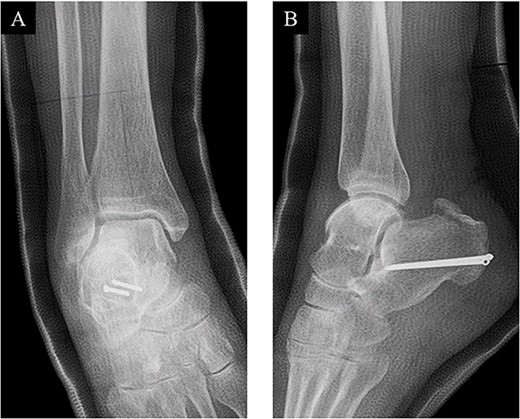

Postoperatively, a non-weightbearing short leg cast was applied for 2 weeks, and when the cast was removed, active and passive ranges of motion exercises of the ankle were started. Partial-weightbearing was allowed at 2 weeks postoperatively, and full-weightbearing at 6 weeks postoperatively. At 3 months after the surgery, non-contrast CT showed complete bone union (Fig. 4). At 2 years after the surgery, she had no symptoms and dysfunctions (Fig. 5).

At 2 years after the surgery, plain radiographs of the right ankle showed complete bone union without the deformity of the fracture site and the backing out of the implants in (A) anteroposterior and (B) lateral views.